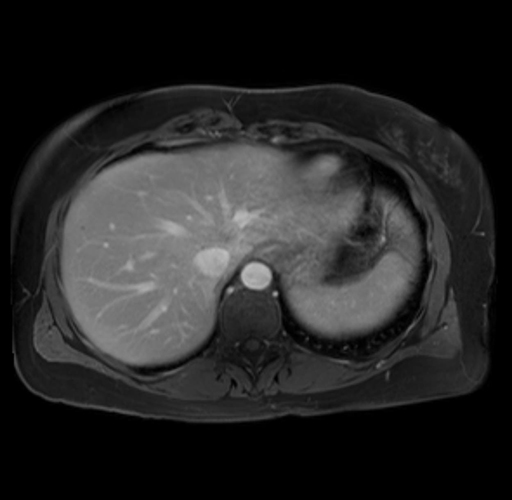

Imaging Analysis

Look through the patient's CT scan to identify any areas of concern for the necessary procedure.

Based on your CT findings, which issue(s) are present and would give reason for "planned slowing down moment(s)" in this case?